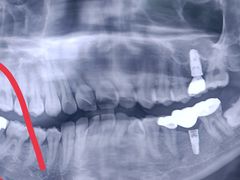

• 牙博士口腔品牌连锁(杨浦店)

艾力克斯_234 | 22-03-19

报错